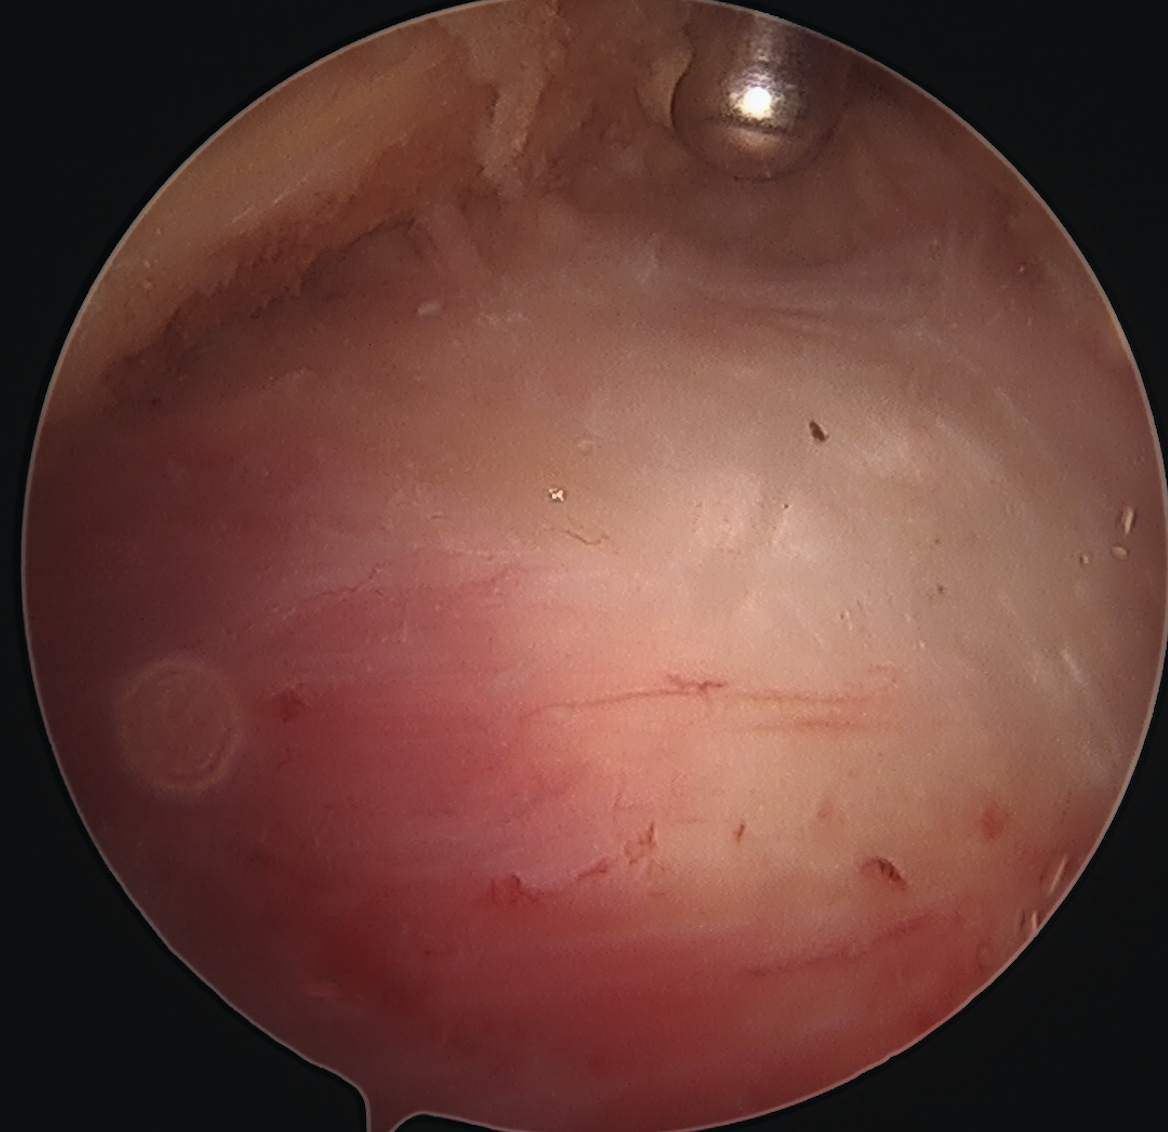

ITB vertical split / cruciform release + trochanteric bursectomy

Arthroscopic technique article

![]()

ITB band Longitudinal split

Cruciform release anteriorly Bursectomy over abductors